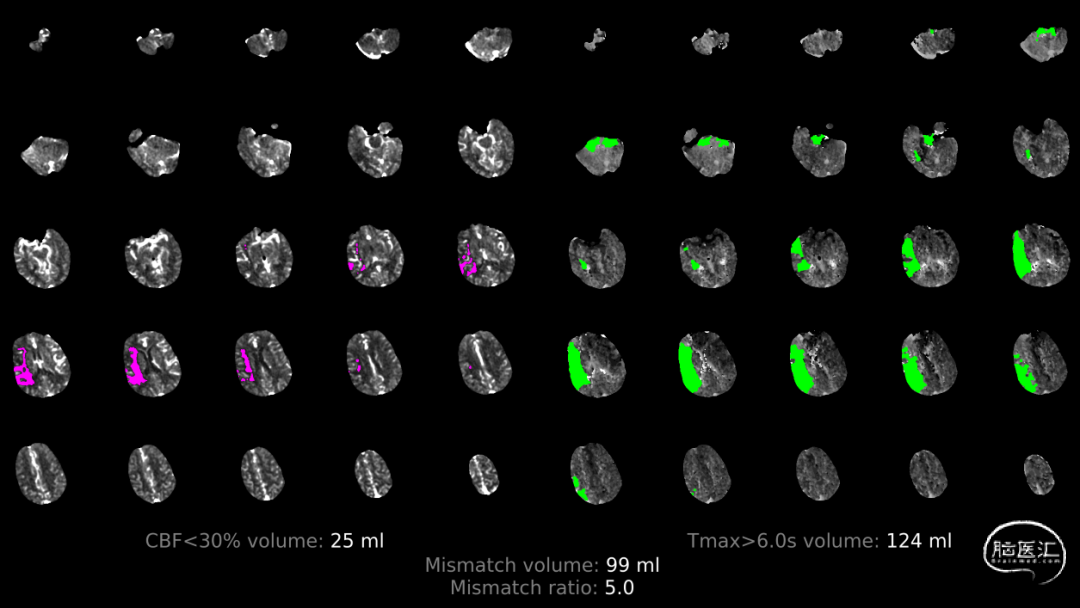

缺血体积124ml,梗死核心25ml